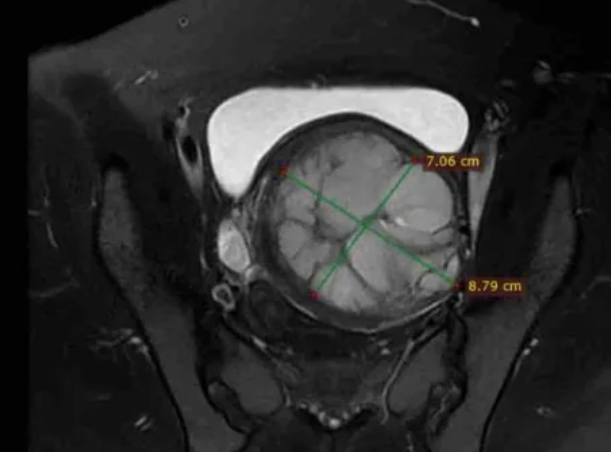

术前MRI平扫及增强扫描可鉴别子宫肌瘤与隐匿性子宫平滑肌肉瘤。弥散加权成像(DWI)高信号、表观弥散系数(ADC)低信号及强化不均是子宫肉瘤的典型影像学表现;MRI的T2加权成像(T2WI)信号可评估消融难度,若T2WI高信号则提示肌瘤含水量高,消融难度通常大于T2WI低信号的病灶。

图:MRI显示一个约9厘米的肿瘤